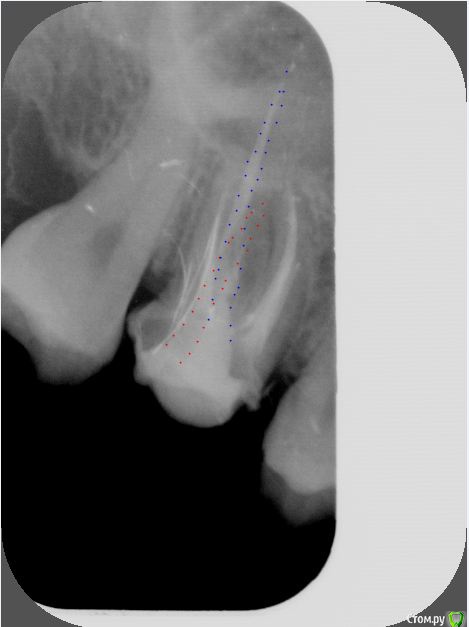

St. Опубликовано 6 июля, 2018 Поделиться Опубликовано 6 июля, 2018 Добрый день. Снимок это плоское изображение обьемных предметов, поэтому могут быть неточности. По предоставленному Вами штифт поставлен не совсем в проекции канала. 1 Ссылка на комментарий

St. Опубликовано 8 июля, 2018 Поделиться Опубликовано 8 июля, 2018 можете на снимке цветом показать свш?Да, конечно Ссылка на комментарий

pocaba Опубликовано 9 июля, 2018 Автор Поделиться Опубликовано 9 июля, 2018 Большое спасибо, St.! Я правильно понимаю, что синими точками выделена проекция канала, а красными - собственно штифт? Ссылка на комментарий

dentikl Опубликовано 9 июля, 2018 Поделиться Опубликовано 9 июля, 2018 Большое спасибо, St.! Я правильно понимаю, что синими точками выделена проекция канала, а красными - собственно штифт?ок.Остаюсь в уверенности,что распаковывая гутту зуб перфорнуть невозможно. Ссылка на комментарий

St. Опубликовано 10 июля, 2018 Поделиться Опубликовано 10 июля, 2018 На снимке до все выглядит прилично. Взять направление на КТ? да, это как минимум разрешит все Ваши сомнения.И в зависимости от его результатов или оставлять временную и понаблюдать как будет зуб вести себя дальше или ставить постоянную Неужели возможно нисколько не почувствовать настолько вышедший за пределы зуба штифт при его установке? Нет, вы неправильно поняли мой ответ. Доктор спрашивал о направлении штифта. И на картинке я нарисовала как мне видится положение штифта и пломбировочного материала. Все это в пределах корня зуба. Ссылка на комментарий